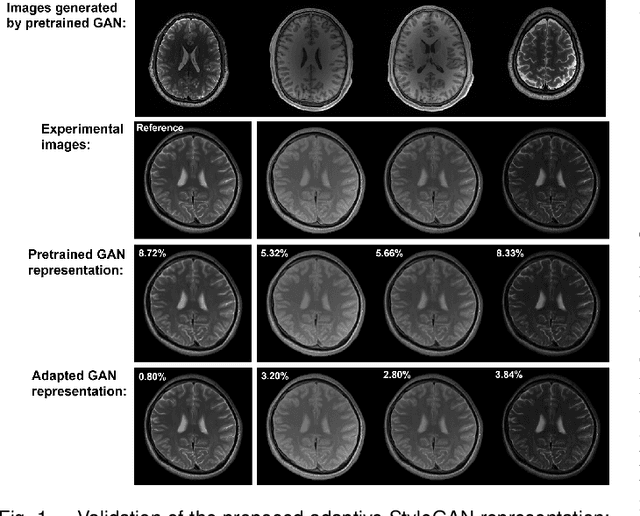

Abstract:We present a novel method that integrates subspace modeling with an adaptive generative image prior for high-dimensional MR image reconstruction. The subspace model imposes an explicit low-dimensional representation of the high-dimensional images, while the generative image prior serves as a spatial constraint on the "contrast-weighted" images or the spatial coefficients of the subspace model. A formulation was introduced to synergize these two components with complimentary regularization such as joint sparsity. A special pretraining plus subject-specific network adaptation strategy was proposed to construct an accurate generative-model-based representation for images with varying contrasts, validated by experimental data. An iterative algorithm was introduced to jointly update the subspace coefficients and the multiresolution latent space of the generative image model that leveraged a recently developed intermediate layer optimization technique for network inversion. We evaluated the utility of the proposed method in two high-dimensional imaging applications: accelerated MR parameter mapping and high-resolution MRSI. Improved performance over state-of-the-art subspace-based methods was demonstrated in both cases. Our work demonstrated the potential of integrating data-driven and adaptive generative models with low-dimensional representation for high-dimensional imaging problems.